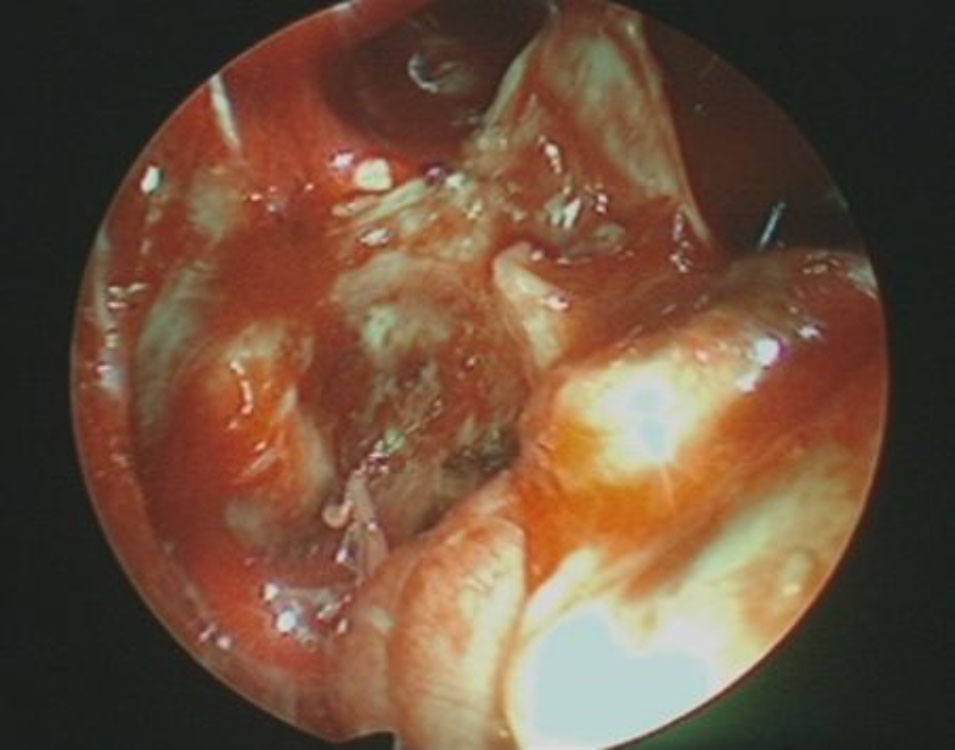

No.’25_108  摘出 中

No.’25_108 摘出 後

右頭頂葉腫瘍

頭蓋内腫瘍摘出術